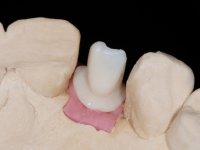

Treatment began with re-preparation of the cast post and core, with the purpose of placing the cervical finishing lines with an intra-sulcular location and simultaneously making a suitable temporary crown. With a very simple orthodontic treatment, the diastema was closed between the upper central incisors, and this position was stabilized with a wire placed on the palatal surface of the central, functioning as containment. Later, a slow orthodontic traction of tooth 2.2 was attempted, in order to reduce, although very slightly, the vertical bone loss in this area. At the end of the traction, tooth 2.2 was extracted and the area was provisionally rehabilitated with a composite resin crown bonded to the adjacent teeth. A dental implant was placed in the area of tooth 2.2 and the temporary crown was again bonded to resin, provisionally rehabilitating the patient during osseointegration. In tooth 1.3 a gingivectomy with an electric scalpel was performed, with the intention of raising the cervical level of 1.3 achieving greater harmony with tooth 2.3. Stabilized soft tissues were impressed using the open tray technique with putty and light addition silicones. Collection of the color of both the dental component and soft tissues was done by the ceramist in the office. In the laboratory, the impressions were transferred to plaster and gave origin to work models that were properly analyzed. It was decided to assemble a metal-ceramic abutment screwed onto the implant. This abutment was cast with a noble alloy and subsequently coated with coronary and gingival ceramics. Due to the inclination of the implant, the screwing inevitably conditioned the exit of the screw hole through the vestibular surface. In order to conceal this situation, the design of the abutment has already been conceived with the intention of accommodating on the vestibular surface the bonding of a feldspathic veneer. This abutment was tested in the mouth and adjustments were made in the gingival ceramic component. Its adaptation to the soft tissues was done in a subtractive way, with a drill, as well as additive, adding resin composed of gingival tonality.

This addition of resin would guide the ceramist in the final placement of the gingival tonality ceramic. The crown that would rehabilitate tooth 1.3 was cemented in this test session with glass ionomer cement, reinforced with composite resin. Once the laboratory work was finished on the veneer for tooth 1.2, the abutment, and the veneer for the implant, this was bonded in the mouth, after placement of the absolute insulation. The work completely satisfied the patient. For eight years, the patient had periodical check-ups, and was pleased with the treatment, but also began to show interest in an aesthetical intervention on the upper central incisors. Once the second phase of our intervention was decided, dental preparation of teeth 1.1 and 2.1 was performed for the placement of two feldspathic veneers. Particular care was taken in the distal inter-proximal preparation adjacent to the abutment of the implant.